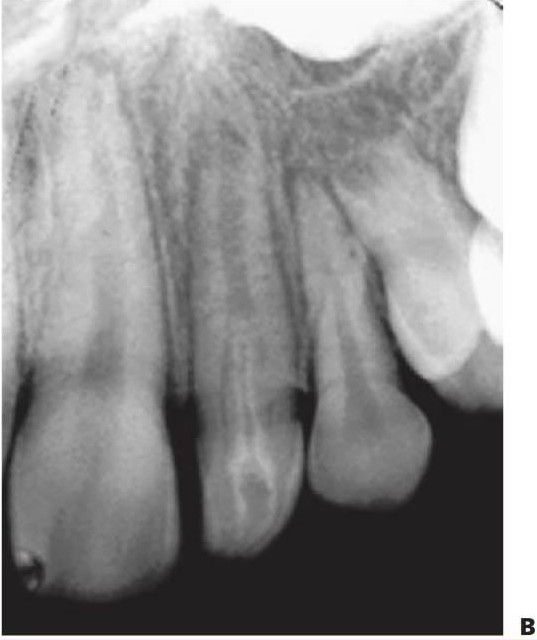

Raquitismo resistente a la vitamina D ligado al cromosoma X (OMIM 307800)

- También conocido como raquitismo ligado al cromosoma X (Xp22) o raquitismo hipofosfatémico hereditario.

- Trastorno ligado al cromosoma X con cambios raquíticos en los huesos largos asociados con un fallo en la reabsorción tubular distal de fosfatos en los riñones. El raquitismo no responde a la vitamina D.

- Estatura corta.

- Piernas arqueadas.

- Varones afectados de forma grave, y las mujeres pueden mostrar características más leves (típicamente estatura corta con piernas arqueadas), a menudo sin afectación de los dientes.

- Fosfato sérico bajo.

- Fosfatasa alcalina elevada (fig.9.31).

Manifestaciones dentales

- La atrición del esmalte incisal y oclusal expone los cuernos pulpares alargados, que a menudo se extienden más allá de la unión amelodentinaria.

- En hombres (y algunas mujeres) se presenta de forma típica con múltiples abscesos en ausencia de caries.

- Cámaras pulpares grandes y retraso en el cierre del ápice radicular.

- En las radiografías puede observarse una menor radiodensidad de la dentina. Puede haber poco esmalte o mostrar algún signo de hipoplasia y/o hipomineralización.

- Estos pacientes pueden someterse a procedimientos ortopédicos reiterados y a una mecánica permanente para promover el reforzamiento o alargamiento del hueso. Tiene mucha importancia mantener un ambiente aséptico, ya que puede requerirse la extracción de los dientes infectados en los momentos en los que el riesgo de infección resulta mayor. El plan de tratamiento debería incluir la colaboración con colegas ortopédicos.